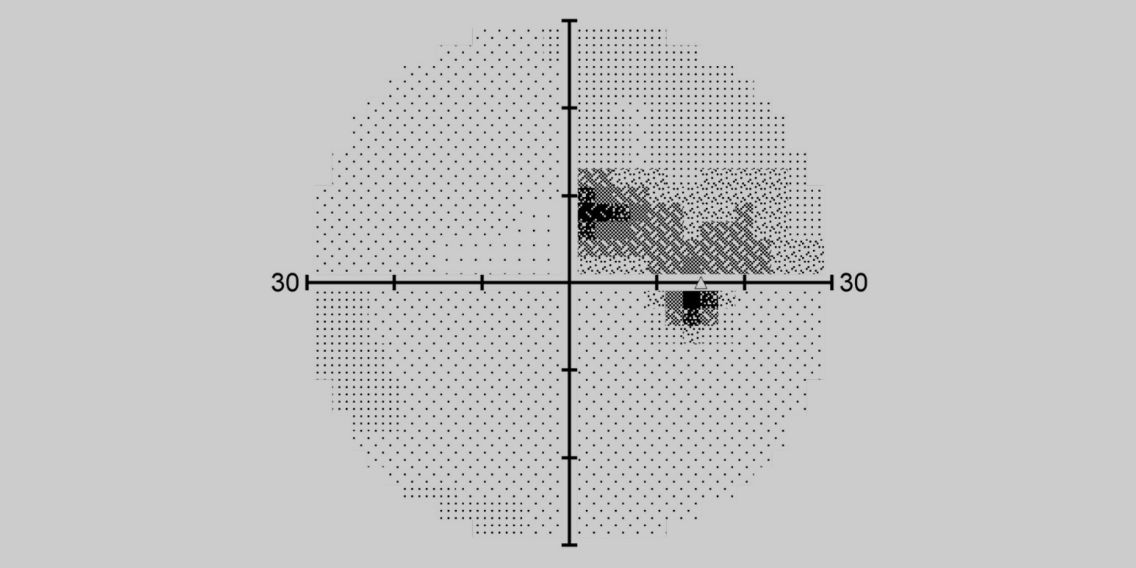

Gesichtsfeldprüfung mit PTS 2000

Mit dem PTS 2000 können wir den Zustand des peripheren Sehens exakt überprüfen und eventuelle Störungen frühzeitig erkennen. Durch präzise Projektionstechniken erhalten wir zuverlässige Daten zur Funktion des gesamten Gesichtsfeldes.